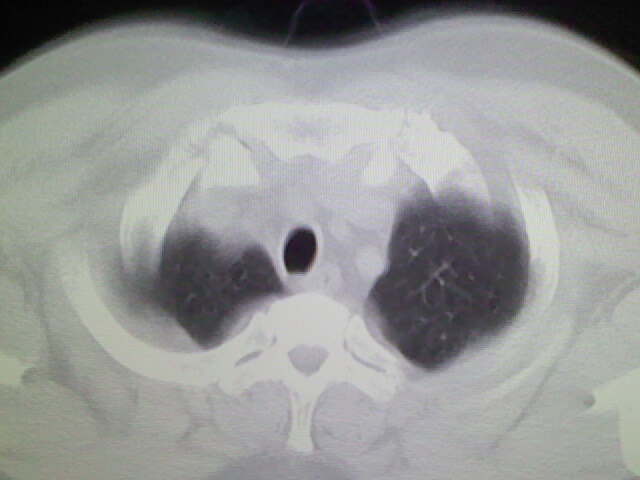

两肺纹理增多,余未见明确异常。

未见明显异常。图像上看此患者比较肥胖,建议查下心超

右侧肺动脉似见密度稍低影,请在机器的薄层上再看看有没有充盈缺损。